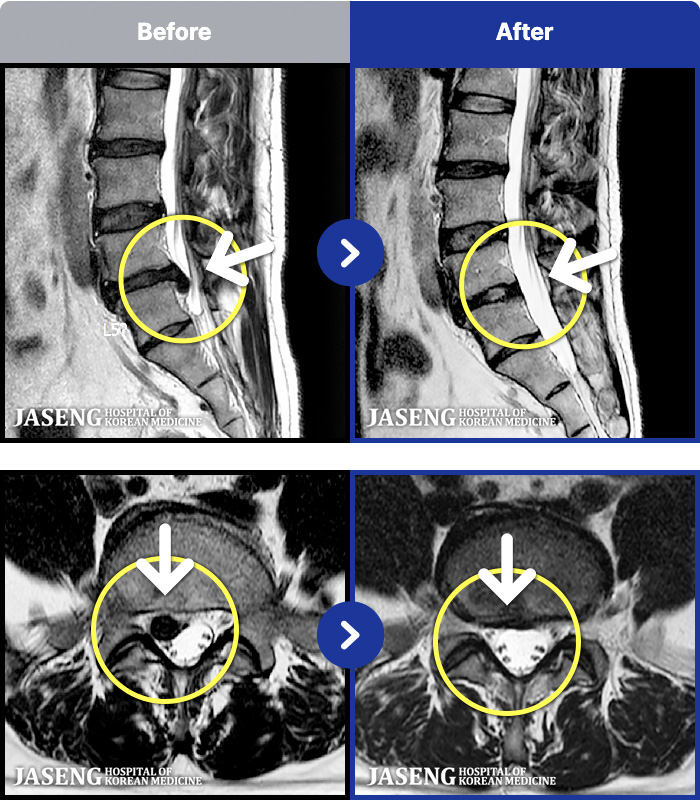

- MRI ġ

MRI ġ

191 MRI ũ ʸ Ȯϼ.

Ƹ ϰ ־.

ȯںп Ǹ ǿ ԿǾ, ο ġ ۿ Ƿ ġḦ Ͻñ ٶϴ.